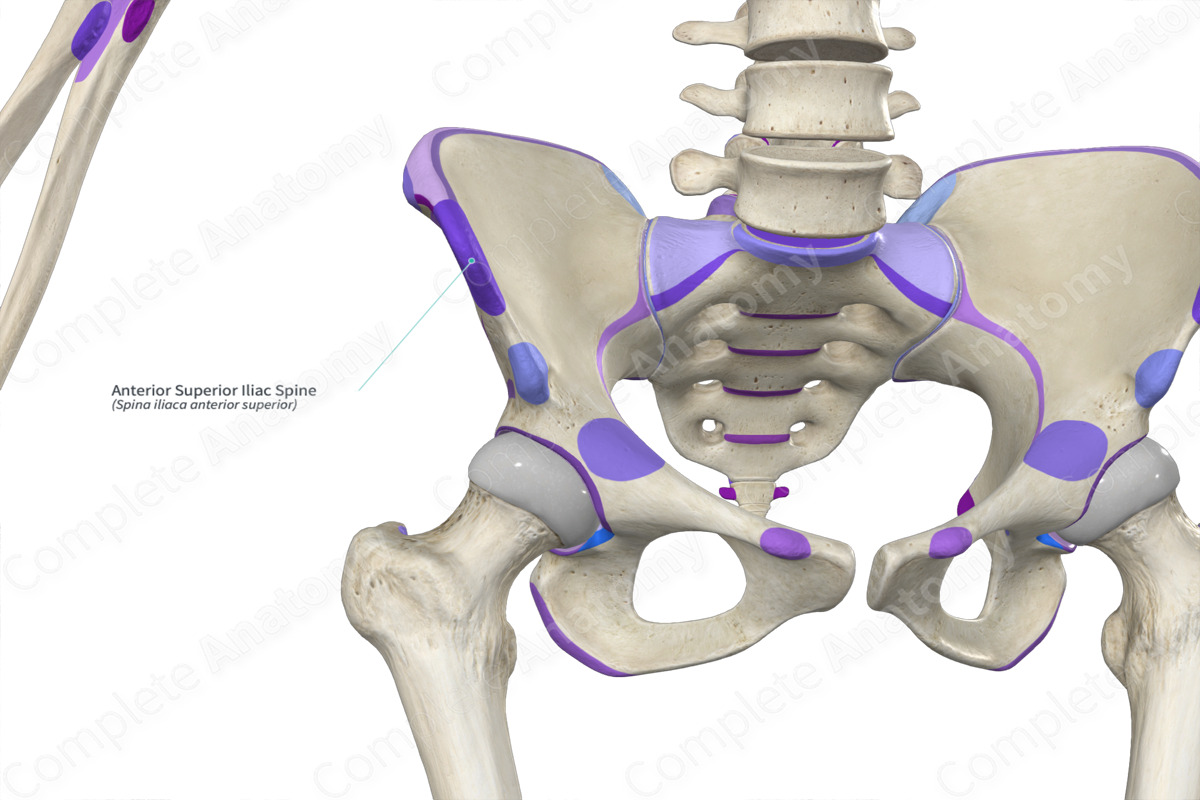

- Key Landmarks:

- Iliac crest

- Anterior superior iliac spine